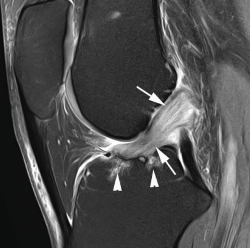

Los hallazgos de RM en las roturas parciales del LCA consisten en un aumento de la señal intrasustancial, defectos focales, distorsión y atenuación de fibras o una orientación anormal del ligamento(1,16)(Figuras 4 y 5). El diagnóstico es más sencillo en fase aguda, por la presencia de signos secundarios con edema y derrame articular. La principal dificultad diagnóstica con RM en la fase aguda consiste en diferenciar roturas parciales de alto grado de completas(1,16).

Figura 4. Rotura parcial del fascículo anteromedial (AM) del ligamento cruzado anterior (LCA) con formación de pequeño ganglión en la escotadura intercondílea. Corte oblicuo coronal (A) y axial (B) de resonancia magnética (RM) potenciados en densidad protónica con supresión grasa que muestran una rotura del fascículo AM (flechas). Fascículo posterolateral normal (cabezas de flecha).

Figura 5. Rotura parcial del fascículo posterolateral (PL) del ligamento cruzado anterior (LCA). Corte oblicuo coronal (A) y axial (B) de resonancia magnética (RM) potenciados en densidad protónica con supresión grasa que muestran una rotura completa proximal del fascículo PL (flechas). Fascículo anteromedial normal (cabezas de flecha).